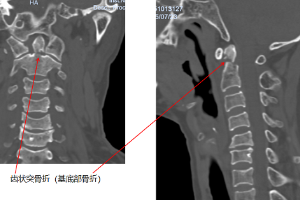

精准导航破难题 微创医术护安康——骨外一科成功救治多发骨折老人

近日,玉溪市人民医院骨外一科依托术中三维C型臂联合骨科手术导航系统,成功为一名伤情复杂的70岁多发骨折老人实施精准微创手术。团队凭借先进设备赋能、多学科协同发力,攻克患者寰枢椎及椎动脉变异带来的手术难题,助力老人早期康复下地,用精湛医术为老年患者生命健康筑起坚实防线。